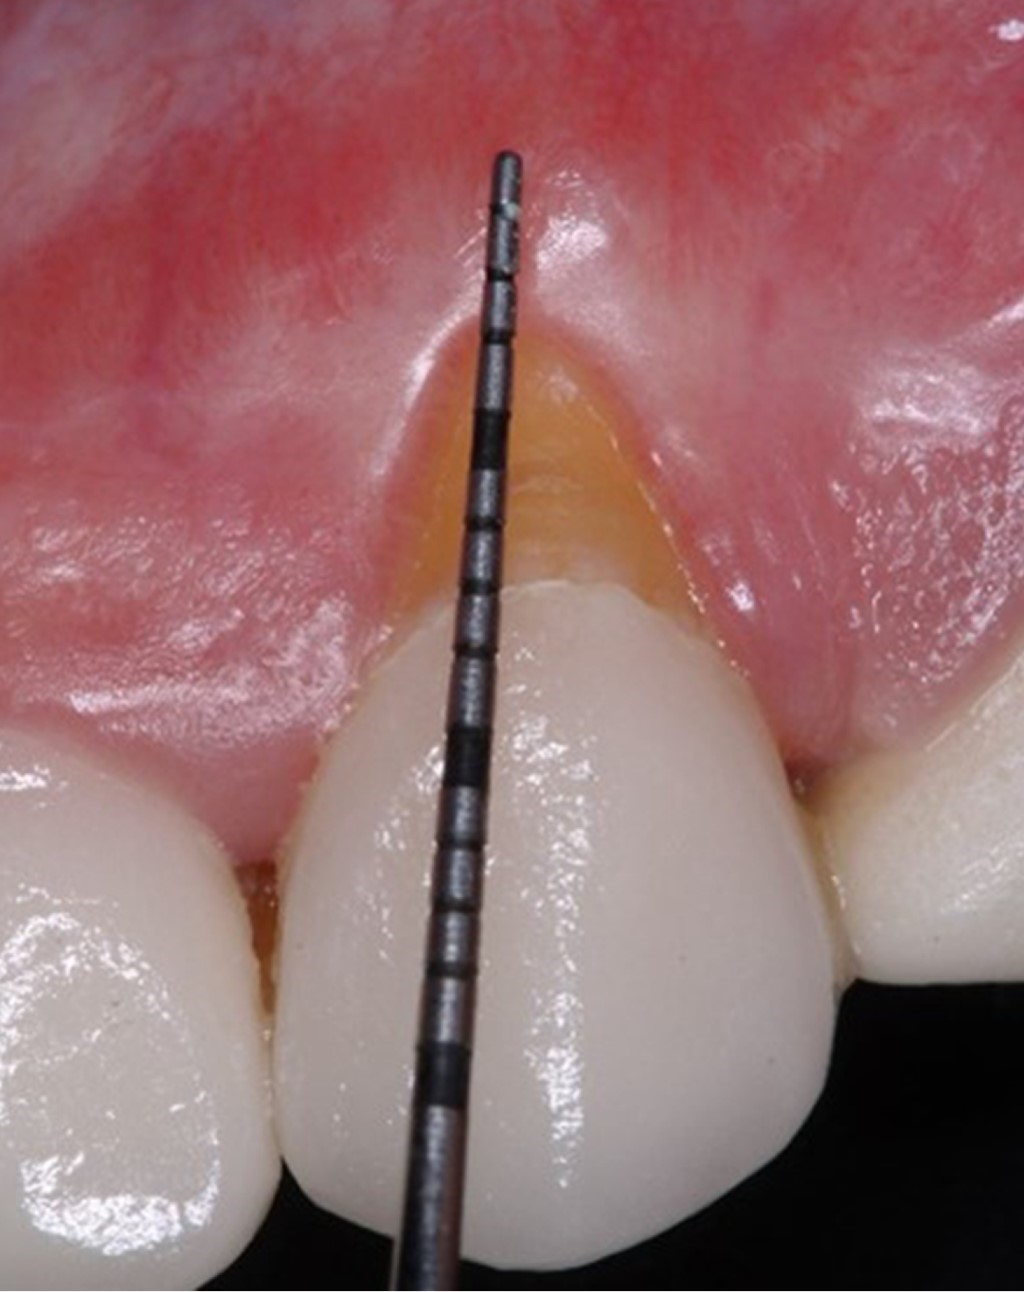

Las papilas anatómicas fueron desepitelizadas con tijeras LaGrange S14® (Figura 4). Luego de la preparación del sitio receptor, se tomaron las medidas del sitio para la obtención del injerto de tejido conectivo, obtenido de la región palatina (sitio donador) mediante cuatro incisiones, al menos 2 mm apicales de distancia del margen gingival de los premolares. De esta forma se obtuvo un injerto libre de tejido conectivo epitelizado, de 10 mm de largo por 4 mm de ancho y 2 mm de grosor (Figura 5). Se eliminó el epitelio de manera extraoral, mediante hojas de bisturí #15.

Las suturas palatinas fueron retiradas a los siete días. En el sitio de la cobertura radicular, las suturas fueron removidas a los 14 días (Figura 8). Se dio seguimiento al paciente a los siete, 14 y 30 días, hasta los seis meses para valoración final, donde se observa cobertura radicular completa (100%), cambio de fenotipo gingival mediante el aumento de tejido queratinizado, mejora en la estética y reducción total de la sensibilidad dental (Figura 9).

Figura 6

Figura 7

Figura 8

Figura 9